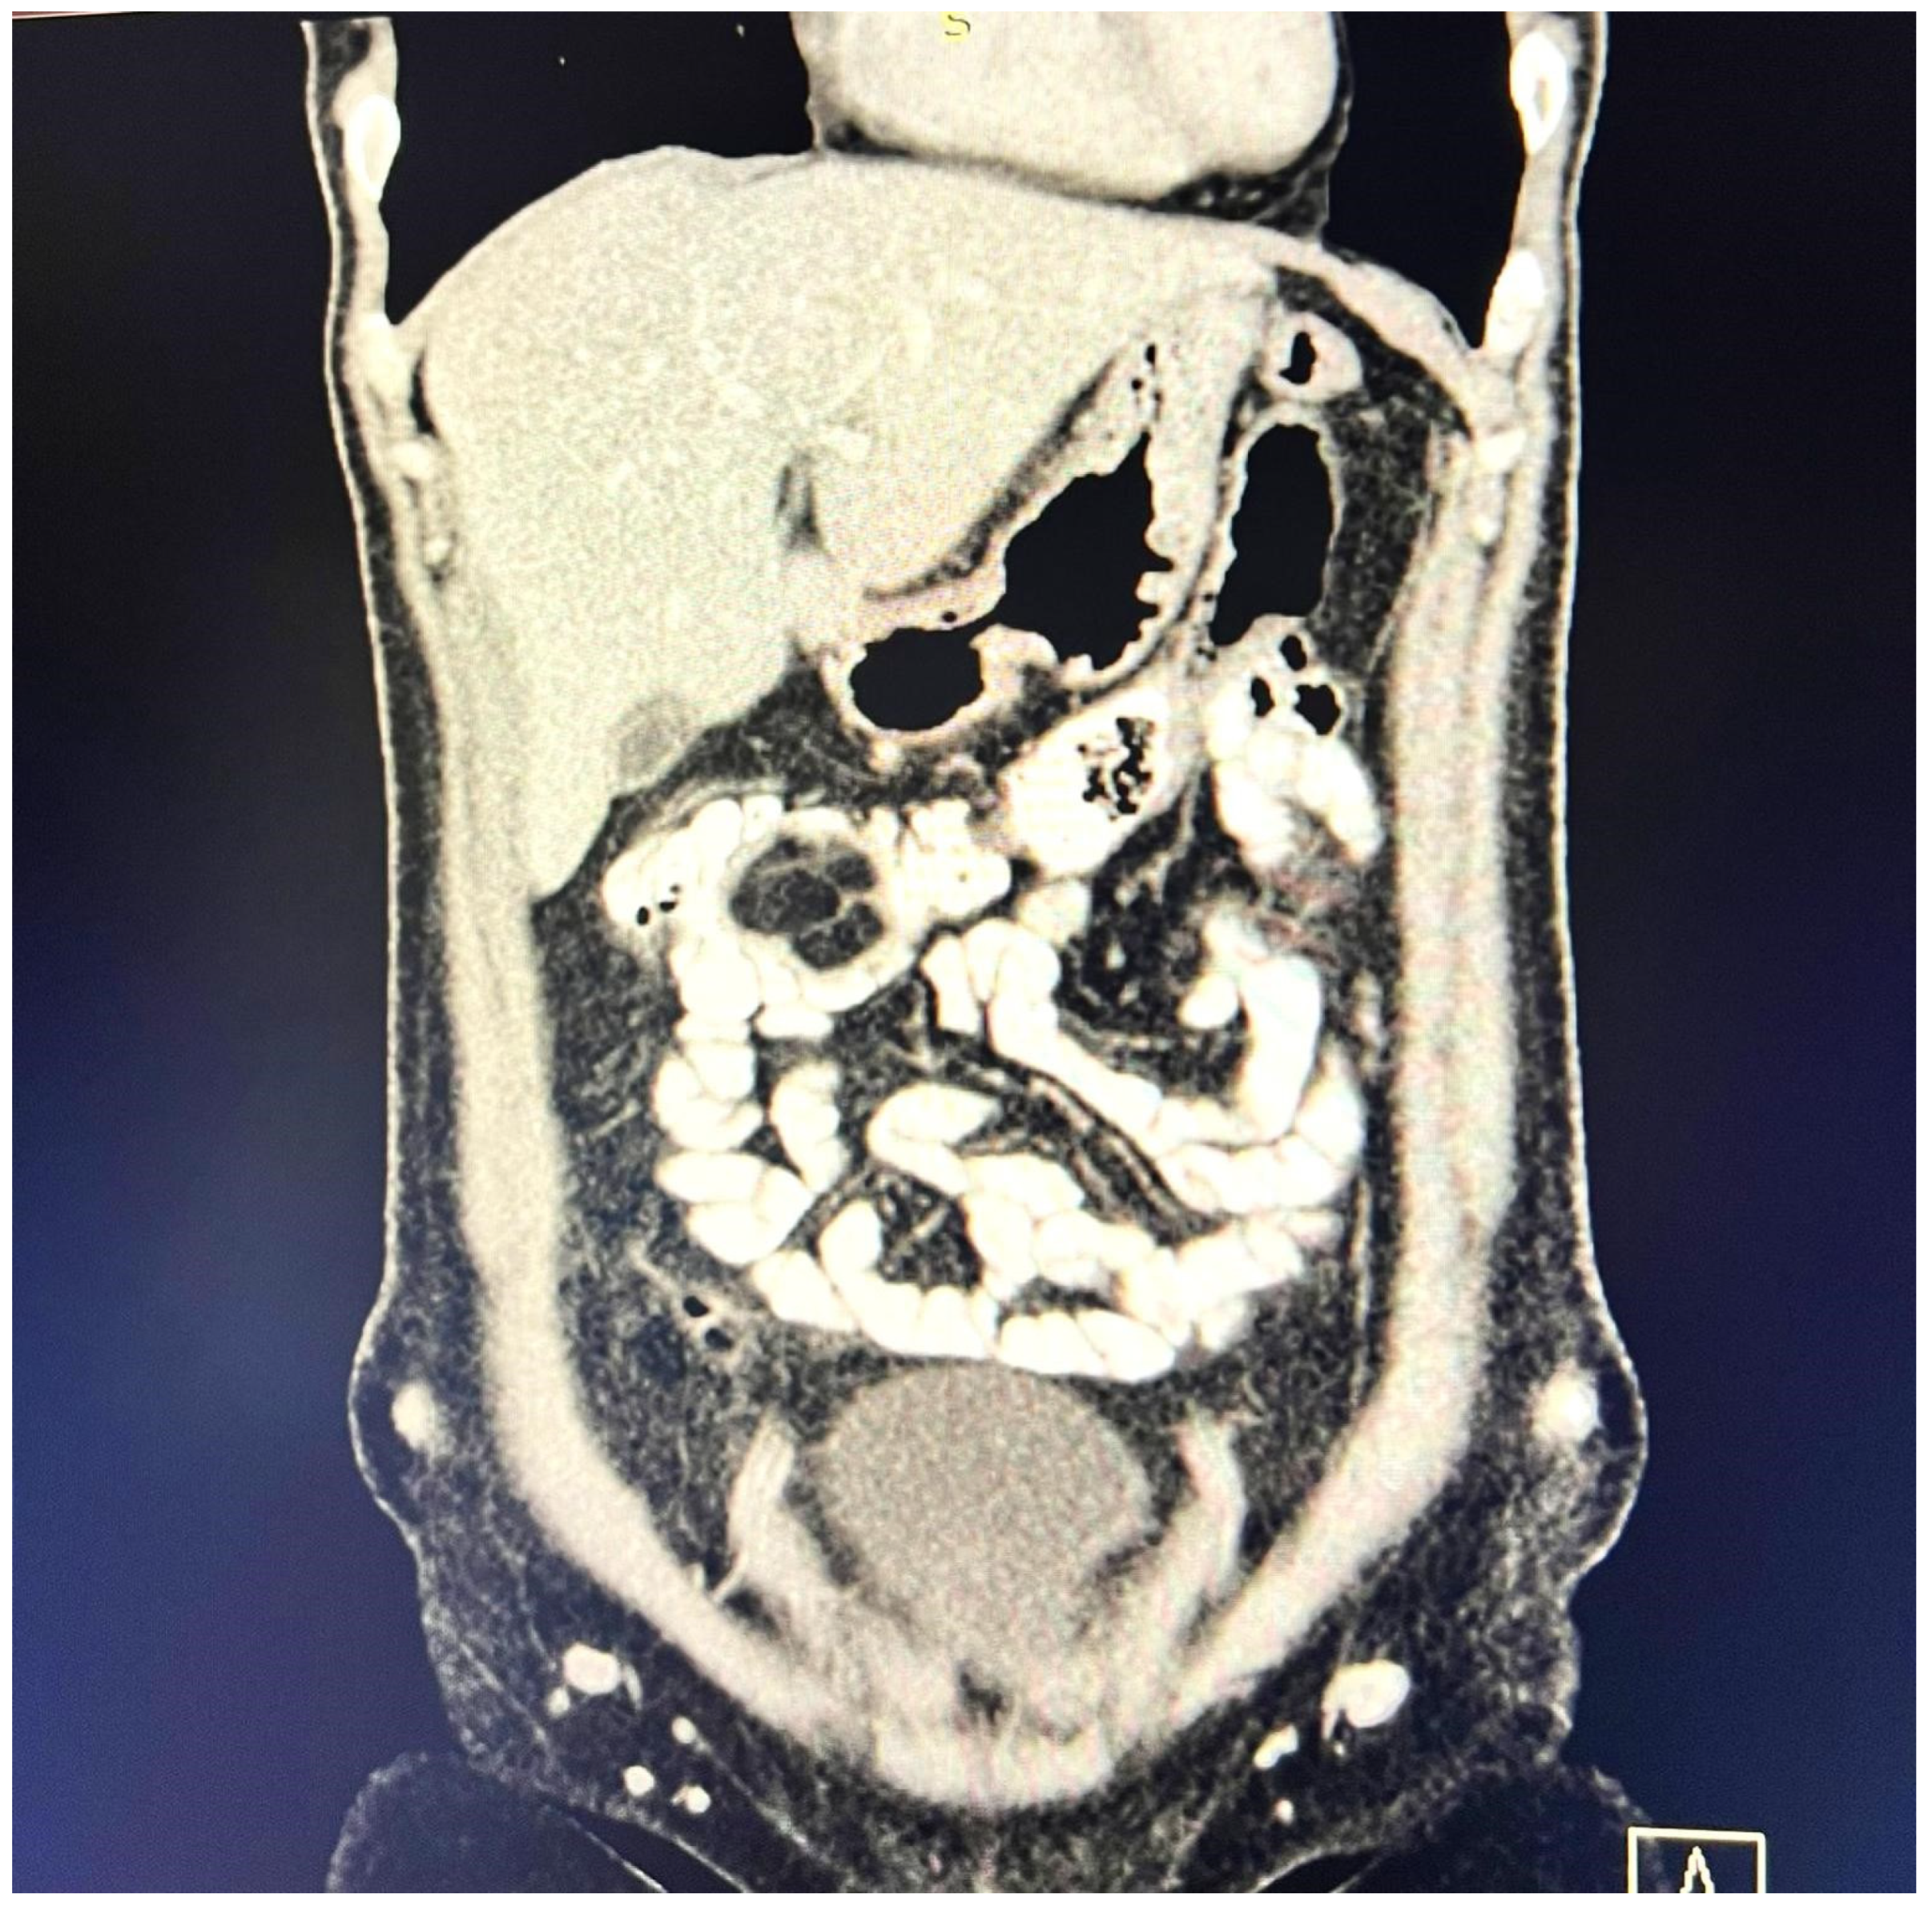

A contrast-enhanced computed tomography (CT) scan conducted on the day of admission revealed circumferential parietal thickening of a maximum of 21 mm at the hepatic flexure of the colon. This thickening extended over a length of approximately 45 mm, resulting in filiform, axial stenosis of the lumen, without any overlying distension of the colonic frame. The parietal thickening was moderately iodophilic and accompanied by discrete linear-type densification of locoregional fat, which was most likely a desmoplastic reaction. A tumor formation with a maximum axial diameter of approximately 29/28 mm, extending craniocaudal on a length of approximately 27 mm, was located at the distal end of the parietal ingrowth with an intraluminal site. This tumor formation had a polycyclic contour, thin septa within, and a discrete lodophilic peripheral appearance. It appeared to have a wide base of implantation at the level of the postero-inferior wall of the colon; mild hepatomegaly in the liver, with a homogeneous structure and a regular surface, and the absence of focal primary or secondary lesions; adenopathies in the hepatic hilum with a maximum diameter of 16/12.5 mm and in the celio-mezenteric territory with a maximum diameter of 24/19 mm; microadenopathies with the gastro-hepatic ligament; and an absence of subdiaphragmatic fluid (Figure 1, Figure 2 and Figure 3).

Figure 2.

Intralumenal mass with an axial diameter of 29/28 mm and extended cranio-caudally over a length of 27 mm, showing polycyclic contour, discretely iodophilic peripherally.